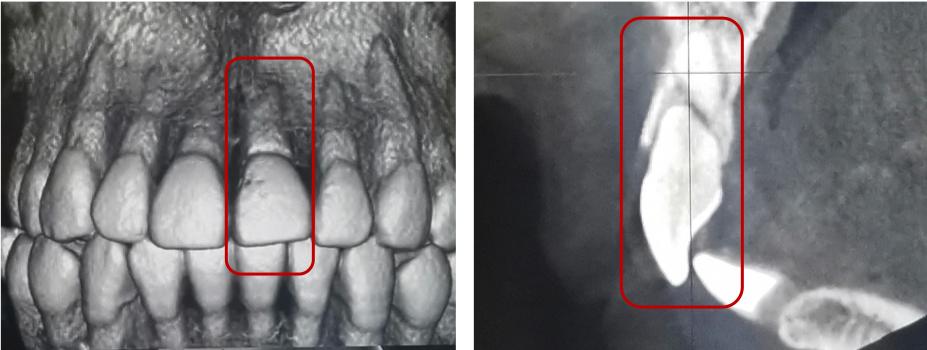

根折--根尖1/3

治疗方案:复位松动移位的断片,弹性夹板固定4周,定期检测折断线愈合情况,监测牙髓状态。牙髓坏死或感染则进行冠方的牙髓治疗。